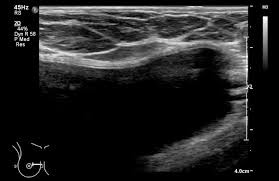

The mass is hypoechoic with posterior shadowing (orange arrow), taller than wide and moderate vascularity. This breast cancer ultrasound image shows changes related to breast cancer that are not seen as microcalcifications or a mass or lump. Other ultrasound findings that suggest breast cancer include: Depending on your symptoms, your doctor makes a diagnosis based on a combination of tests and procedures. This can make it harder for your radiologist to spot signs of breast cancer, since dense tissue and tumors both look white in mammogram images.

Breast ultrasound images are seen from superficial (skin) to deep (chest wall muscle) over a segment of tissue. Other ultrasound findings that suggest breast cancer include: Looks larger, thicker or heavier. Other ultrasound findings that suggest breast cancer include: Presenting radiologic appearance of breast dcis microcalcifications at breast cancer screening we can see from the chart above that overall, the most commonly occuring mammographic indication of dcis are the crushed stone microcalcifications. This can make it harder for your radiologist to spot signs of breast cancer, since dense tissue and tumors both look white in mammogram images. While it may look like a fuzzy, spotty television screen with different shades of grey to a patient, the ultrasound technician and the radiologist use these images to diagnose masses and tumors. Any area that does not look like normal tissue is a possible cause for concern.

Ultrasound does not use or. Inflammatory breast cancer pictures and symptoms. As the machine is moved over an area of the breast, the device sends sound waves into the tissue, and it shows an image based on how quickly those waves bounce back to it. Both the mammogram and ultrasound looked fuzzy and gray on the screen and i have no idea. Ultrasound images are black and white, showing a small portion of the breast at a time.